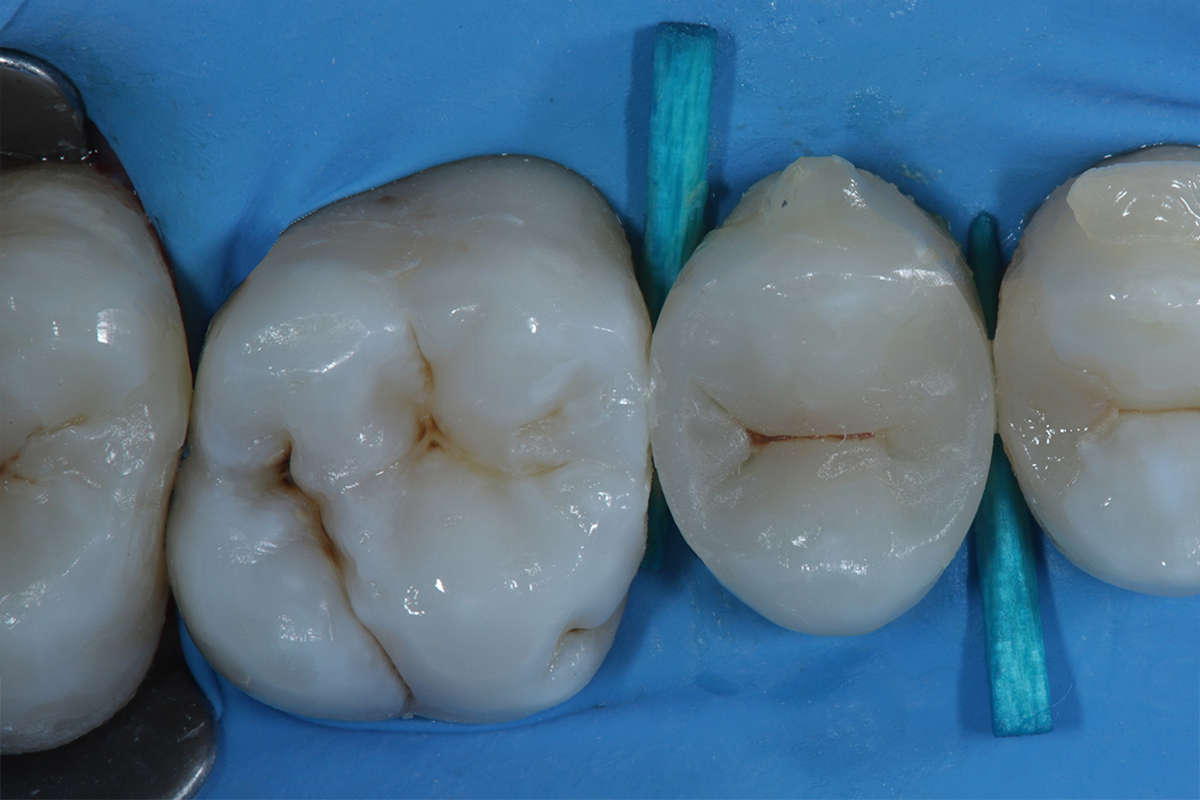

La corretta selezione dei cunei interdentali in odontoiatria restaurativa è fondamentale per la precisione ed il successo a lungo termine del restauro. Infatti, i cunei sono strumenti essenziali ne

La corretta selezione dei cunei interdentali in odontoiatria restaurativa è fondamentale per la precisione ed il successo a lungo termine del restauro. Infatti, i cunei sono strumenti essenziali nel garantire un corretto adattamento della matrice al gradino cervicale, nel ridurre la formazione di debordi, nel promuovere un’emergenza anatomica e nel contribuire alla creazione di una perfetta area di contatto.

Questo articolo esamina le funzioni biomeccaniche dei cunei e analizza i vantaggi delle soluzioni più moderne, tra cui 3D Fusion™, Strata-G™, Wedge Wands™, rispetto ai cunei tradizionali in legno.

Al contrario, dispositivi moderni come 3D Fusion™, Strata-G™ e Wedge Wands™, sono progettati per offrire una combinazione di forza di separazione calibrata, adattamento tridimensionale ed ergonomia di inserimento. I materiali sintetici utilizzati non si deformano in modo imprevedibile e mantengono la loro forma e funzione per tutta la durata del restauro. La presenza di superfici anatomiche flessibili, come nel caso del sistema 3D Fusion™ e Strata-G™, permette un ottimale adattamento della matrice al gradino cervicale riducendo significativamente il rischio di debordi e migliora la qualità del punto di contatto. Le sistematiche 3D Fusion™ e Strata-G™ grazie alla loro morfologia sigillano in modo adattivo e tridimensionale anche in presenza di concavità radicolari. Questa tipologia di cunei trova indicazione nella quasi totalità della casistica clinica di tutti i giorni. In particolar modo risulta più semplice il restauro in presenza di gradini cervicali concavi, grazie al design e alla struttura siliconica flessibile.

I cunei 3D Fusion™ offrono potenza, controllo e precisione: hanno una maggiore capacità di separazione interdentale e mantengono la forza di separazione durante tutta la procedura. Questi cunei combinano una struttura centrale rigida con delle ali laterali morbide, che si espandono per adattarsi alla forma dello spazio interdentale, garantendo al tempo stesso ottima stabilità e adattamento gengivale. Tuttavia, rispetto

agli Strata-G, i 3D Fusion sono meno indicati negli spazi estremamente stretti, dove la loro struttura più voluminosa potrebbe rendere difficile l’inserzione o risultare troppo invasiva per i tessuti gengivali.

I cunei Strata-G™ puntano invece su morbidezza, adattabilità e protezione dei tessuti, la loro flessibilità li rende atraumatici e quindi ideali in presenza di papille delicate o spazi particolarmente angolati o limitati. La loro forma anatomica è pensata per inserirsi agevolmente negli spazi interdentali più stretti, seguendo il profilo della papilla gengivale senza comprimerla eccessivamente. Anche i cunei strata-G presentano delle alette morbide che consentono un perfetto adattamento in caso di cavità concave ed irregolari. Le migliori performance cliniche e l’integrazione sinergica si ottengono in combinazione con le matrici e gli anelli separatori (3D fusion o Strata G).